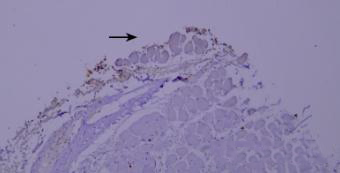

干片导致的假阴性(黑色箭头区域)。

优化建议:

加入Tween-20的缓冲液能够更好地防止切片干燥。